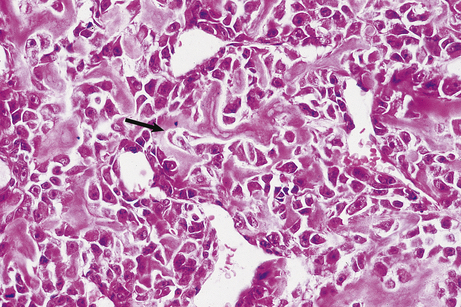

As with carcinomas, sarcomas can be further categorised according to their grade or degree of differentiation (Fig. 11.15).

image

Fig. 11.15 Osteosarcoma. Histology showing pleomorphic tumour cells sufficiently differentiated to produce the amorphous pink-stained osteoid (arrow) lying between them.